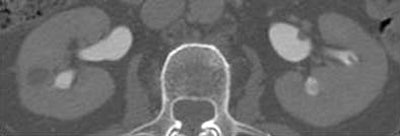

| Parenchymal phase (above), excretory phase (below), and MIP images (bottom) from a patient with a high-grade superficial recurrence of transitional cell carcinoma in the left renal pelvis. Images courtesy of Dr. Theresa Koppie. |

The researchers evaluated the CT images for hydronephrosis, filling defects, strictures, thickening, renal pelvis, ureters, anastomosis, and periureteral soft-tissue changes. They found 13 cases of hydronephrosis, nine patients with filling defects ranging from 5 mm to 1.5 cm, and seven patients with periureteral stranding. Periureteral stranding occurred most commonly in the distal left ureter in the region where it crossed the left mesentery, she said. Calculi were found in two patients. Eight of the 47 patients had cancer recurrence, all histologically proven transitional-cell carcinomas obtained during open surgery, Koppie said.

"All of the patients who developed some kind of a cancer in the upper tracts (renal pelvis, calyces, ureter) had a positive CT urogram," Koppie said. CT was 100% sensitive, and 30.8% specific, for upper-tract disease recurrence.